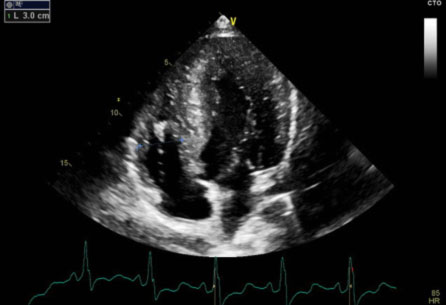

La sindrome di Noonan